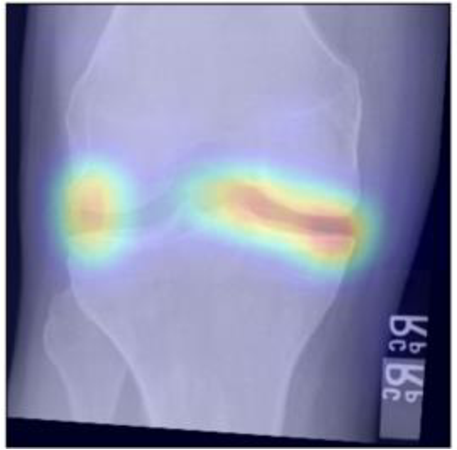

To gain insight into the basis of the CNN’s prediction, we used the GradCAM [24] approach and visualized the attention maps for the well-predicted knees. Examples of attention maps are presented in Figure 5. We observed that in various cases, the CNN paid attention to the compartment opposite to the one where degenerative change became visible during the follow-up visits. Additional examples of such attention maps are presented in Supplementary Figures 3, 4, 5 and 6.

Refer to caption

(a)

(b)

(c)

(d)

Figure 5: Examples of attention maps for progression cases and the corresponding visualization of progression derived using follow-up images from MOST datasets. Here, subplots (a) and (c) show the attention maps derived using a GradCAM approach. Subplots (b) and (d) show the joint-space areas from all the follow-up images (baseline to 84 months). Here, the subplot (b) corresponds to the attention map a) and the subplot (d) corresponds to the attention map (c).